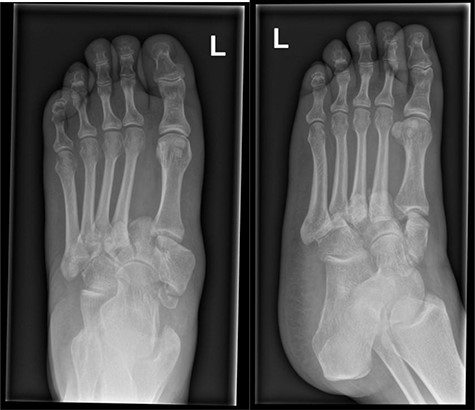

Initial foot X-rays (AP and lateral views), exhibiting normal appearances.

A 41-year-old female, with a background of Type 1 Diabetes Mellitus (T1DM), previous diabetic foot infection and peripheral neuropathy, presented acutely with a hot, swollen and erythematous left foot. Ten days prior, she sustained a fall whilst walking. The patient denied injury, swelling or pain at the time, though she presented to the emergency department (ED) 2 days following the fall with a new-onset foot swelling. Initial imaging with plain film X-ray, as well as blood tests, was unremarkable (Fig. 1), and she was discharged from the ED. A plantar blister appeared over the following days, with subsequent worsening of foot swelling and erythema over a 10-day period, culminating in her acute presentation (Fig. 2).